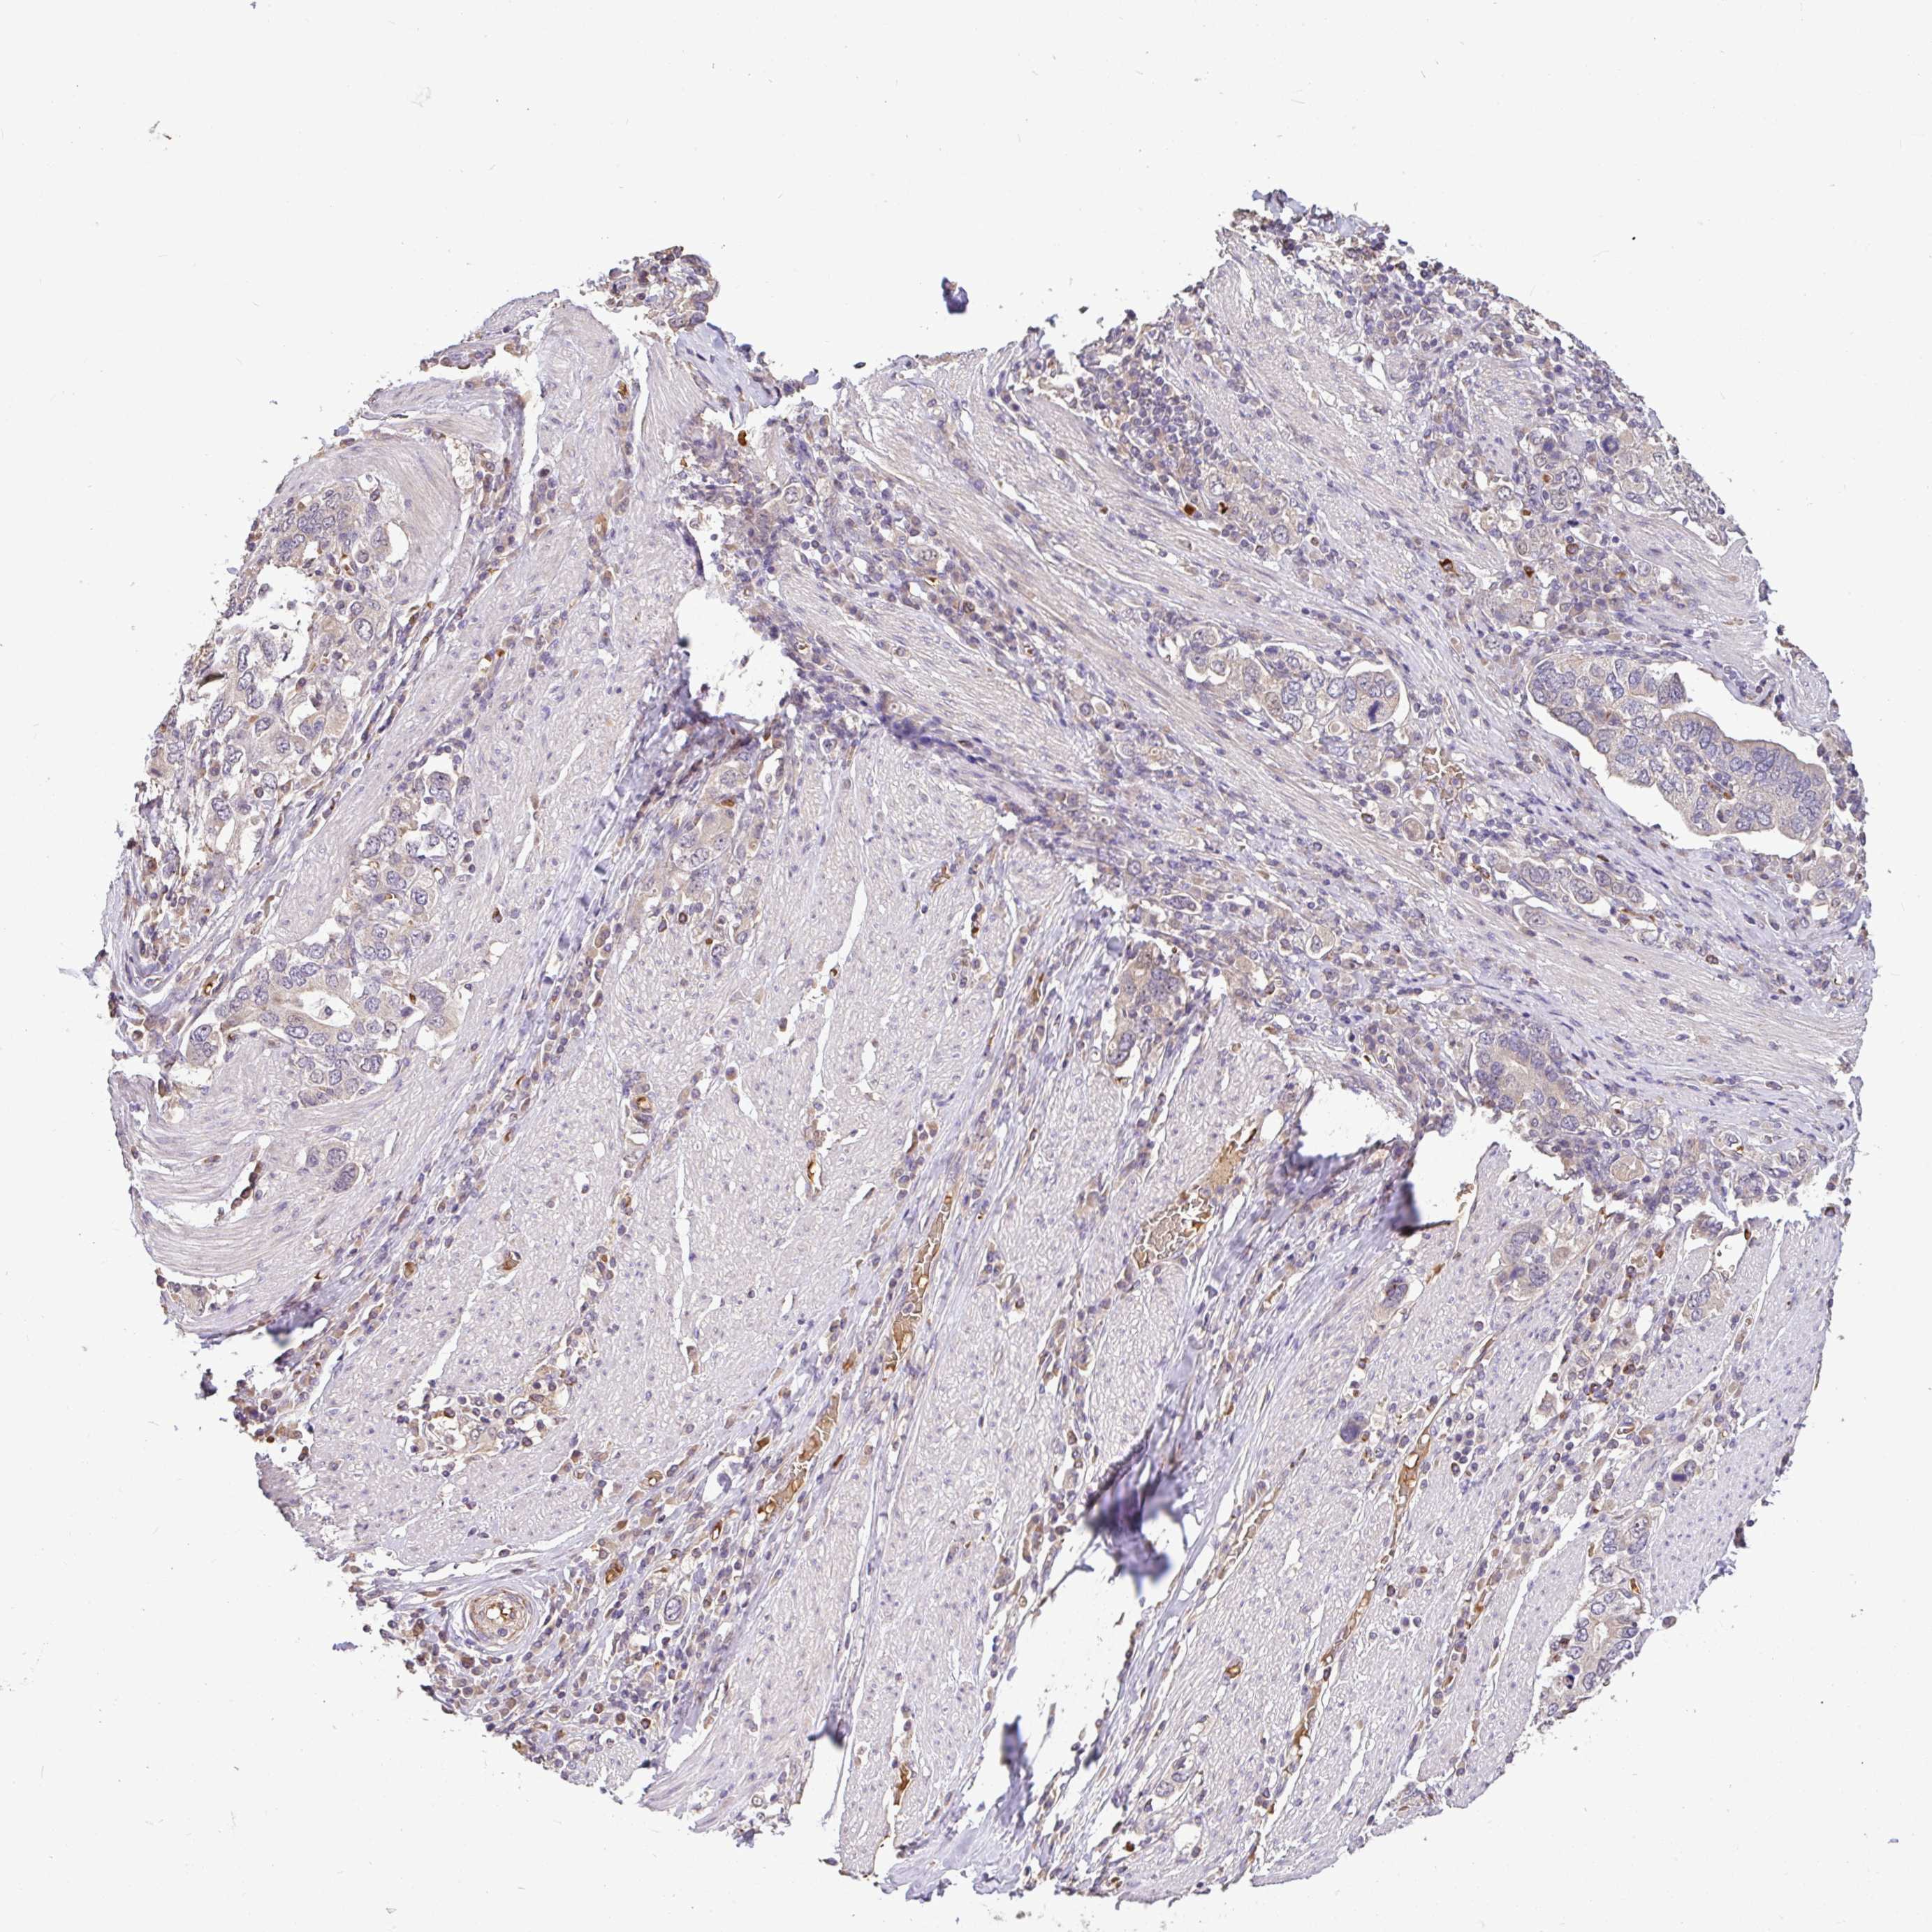

STOMACH CANCER - Protein expressioni

A mouse-over function shows sample information and annotation data. Click on an image to view it in a full screen mode. Samples can be filtered based on level of antibody staining by selecting one or several of the following categories: high, medium, low and not detected. The assay and annotation is described here.

Antibody stainingi

Antibody staining in the annotated cell types in the current human tissue is reported as not detected, low, medium, or high, based on conventional immunohistochemistry profiling in selected tissues. This score is based on the combination of the staining intensity and fraction of stained cells.

Each image is clickable and will lead to virtual microscopy that enables deeper exploration of all samples and also displays staining intensity scores, fraction scores and subcellular localization as well as patient and tissue information for each sample.

Antibody HPA056632

Staining

High

Medium

Low

Not detected

Intensity

Strong

Moderate

Weak

Negative

Quantity

>75%

75%-25%

<25%

None

Location

Nuclear

Cytoplasmic/membranous

Cytoplasmic/membranous,nuclear

Adenocarcinoma, NOS